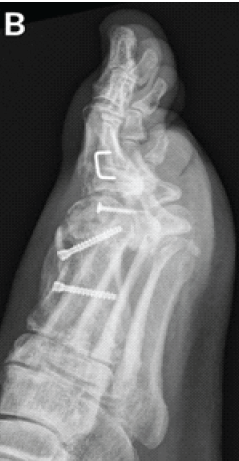

Surgical Management of Painful Os Vesalianum: A Case Report and Literature Review

Venkataramana Kuruba , Vignesh Chandrasekar , Abhinay Vadlamudi , Elandevan Gunasekaran , V T Abraham , A R Nataraj